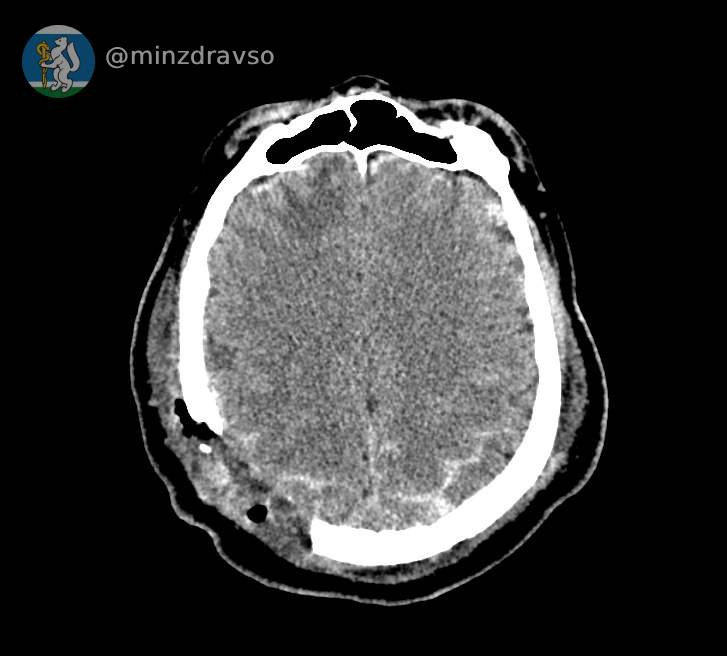

В Серове 57-летнего мужчину ударила стрела строительного крана, расколов ему череп. В критическом состоянии мужчина поступил в единственное на севере нашего региона стационарное отделение скорой медицинской помощи, действующее на базе Серовской городской больницы. Высокоточный компьютерный томограф помог быстро диагностировать травмы и выявить расположение повредивших мозг костных отломков, самый острый из которых мог в любую минуту стать причиной гибели пациента. Слаженное взаимодействие серовских реаниматологов позволило стабилизировать состояние пострадавшего.

Профильные специалисты из Екатеринбурга в ходе телеконсультации подтвердили необходимость перегоспитализации уральца в ближайший межмуниципальный медицинский центр. Мужчину экстренно доставили в Городскую больницу №1 Нижнего Тагила, где его ожидала операционная бригада. Нейрохирург Дмитрий Неволин, анестезиолог-реаниматолог Аслам Абдуев и операционная медсестра Нина Дмитриева удалили отломки костей, гематомы, восстановили целостность твёрдой мозговой оболочки.